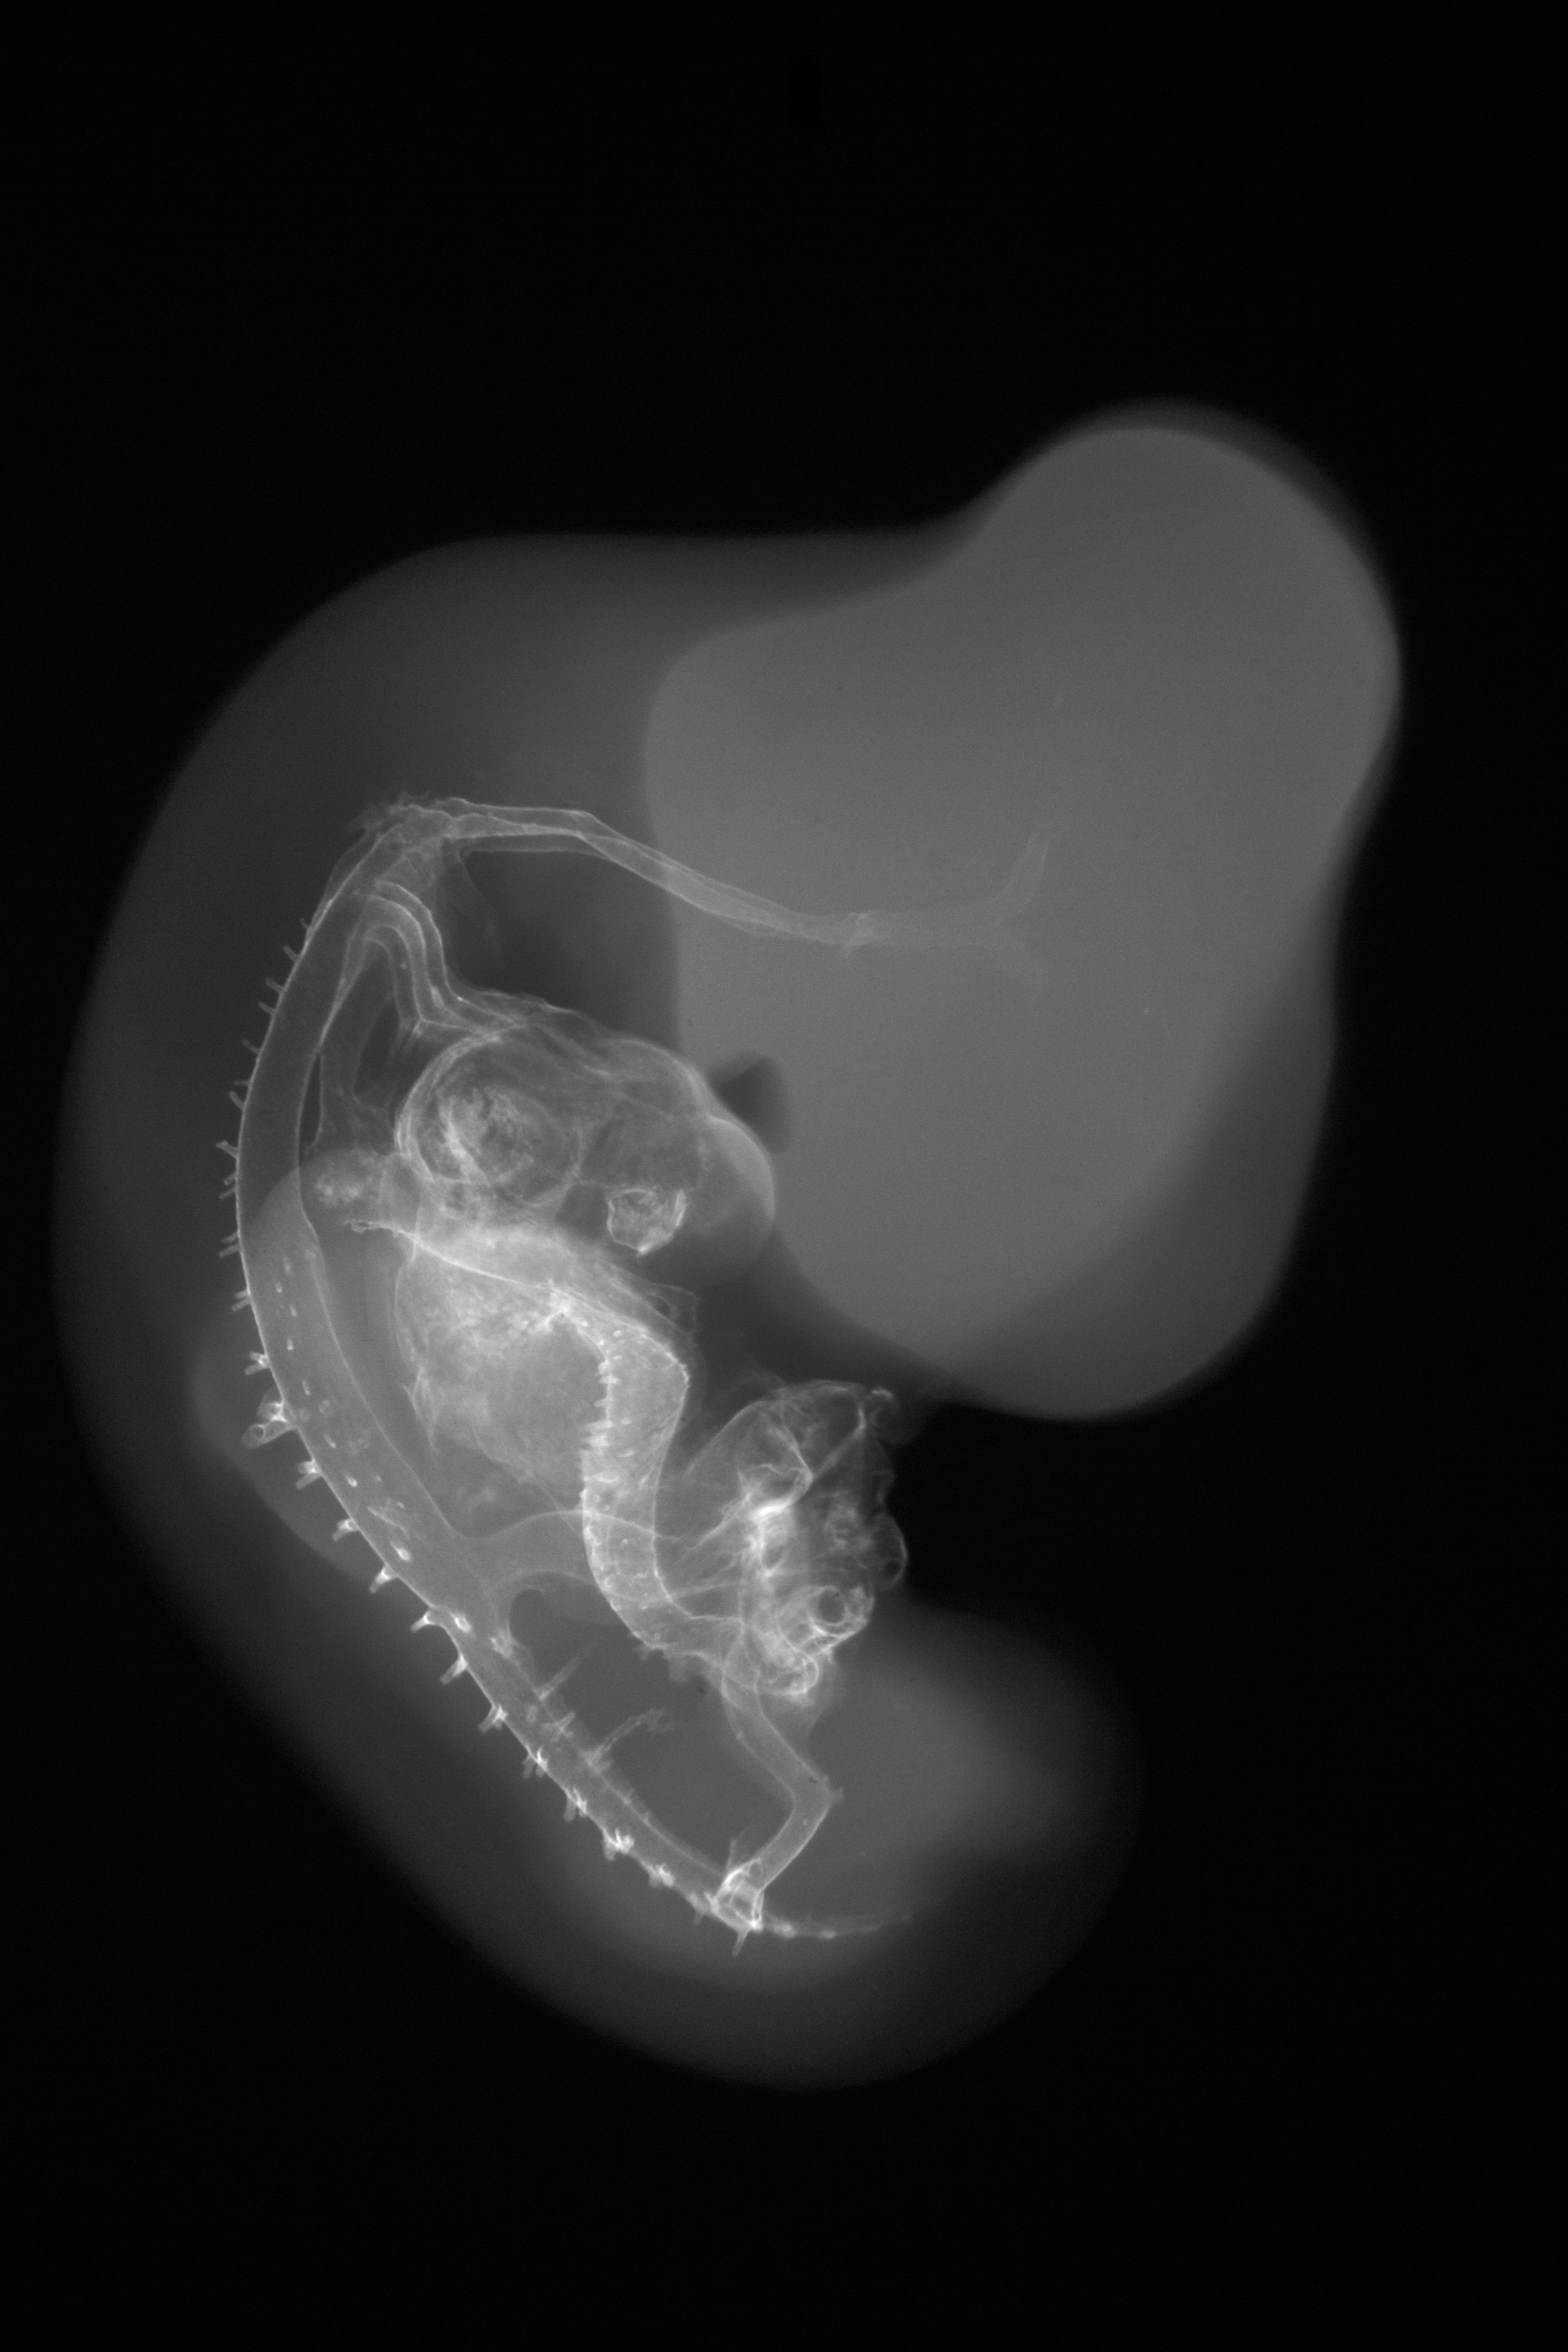

Chick Embryo Microangiography

Hamburger-Hamilton (HH) Stage 27 (approx. 5 - 5.5 days)

Stereo X-Ray Micrographs